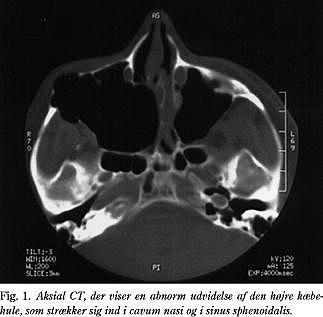

Når man trykkede på højre processus zygomaticus, fremkom der samme lyd, som når man presser bunden ind på en blikdåse. CT og MR-scanning viste abnorm udvidelse af højre sinus maxillaris. Udvidelsen omfattede cavum nasi, sinus sphenoidalis og orbita (Fig. 1 ). Der blev udført funktionel endonasal sinuskirurgi (FESS) i generel anæstesi. Kæbehulens medialvæg, svarende til området over concha inferior, blev reseceret, hvorved et større neoostie til kæbehulen blev dannet. Det bemærkedes, at ved at applicere et tryk mod bulbus oculi sås der i endoskopet tydelig mobilitet af gulvet i højre orbita. En efterfølgende histologisk undersøgelse viste ødem og let metaplasi af sinusmukosa. Ved en ambulant kontrol 15 måneder postoperativt var patienten symptomfri, og man fandt ingen exophtalmus eller hævelse af højre ansigtshalvdel. En CT viste aftagende volumen af højre sinus maxillaris. Da patienten postoperativt havde givet udtryk for betydelig bekymring for fornyede symptomer i forbindelse med planlagte flyrejser, blev han 15 måneder efter operationen udsat for simuleret højdeklima ved at blive anbragt i Rigshospitalets over- og undertrykskammer (Fig. 2 ). Trykket blev reduceret til 0,528 ATA, svarende til en ukompenseret flyvehøjde på 4.000 meter. Der konstateredes herved fuldstændig trykudligning i sinus, idet patienten ikke havde symptomer under testen.